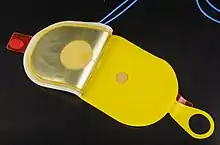

Self-adhesive electrodes

Newer types of resuscitation electrodes are designed as an adhesive pad, which includes either solid or wet gel. These are peeled off their backing and applied to the patient's chest when deemed necessary, much the same as any other sticker. The electrodes are then connected to a defibrillator, much as the paddles would be. If defibrillation is required, the machine is charged, and the shock is delivered, without any need to apply any additional gel or to retrieve and place any paddles. Most adhesive electrodes are designed to be used not only for defibrillation, but also for transcutaneous pacing and synchronized electrical cardioversion. These adhesive pads are found on most automated and semi-automated units and are replacing paddles entirely in non-hospital settings. In hospital, for cases where cardiac arrest is likely to occur (but has not yet), self-adhesive pads may be placed prophylactically.

Pads also offer an advantage to the untrained user, and to medics working in the sub-optimal conditions of the field. Pads do not require extra leads to be attached for monitoring, and they do not require any force to be applied as the shock is delivered. Thus, adhesive electrodes minimize the risk of the operator coming into physical (and thus electrical) contact with the patient as the shock is delivered by allowing the operator to be up to several feet away. (The risk of electrical shock to others remains unchanged, as does that of shock due to operator misuse.) Self-adhesive electrodes are single-use only. They may be used for multiple shocks in a single course of treatment, but are replaced if (or in case) the patient recovers then reenters cardiac arrest.

Special pads are used for children under the age of 8 or those under 55 lbs. (22 kg).[22]